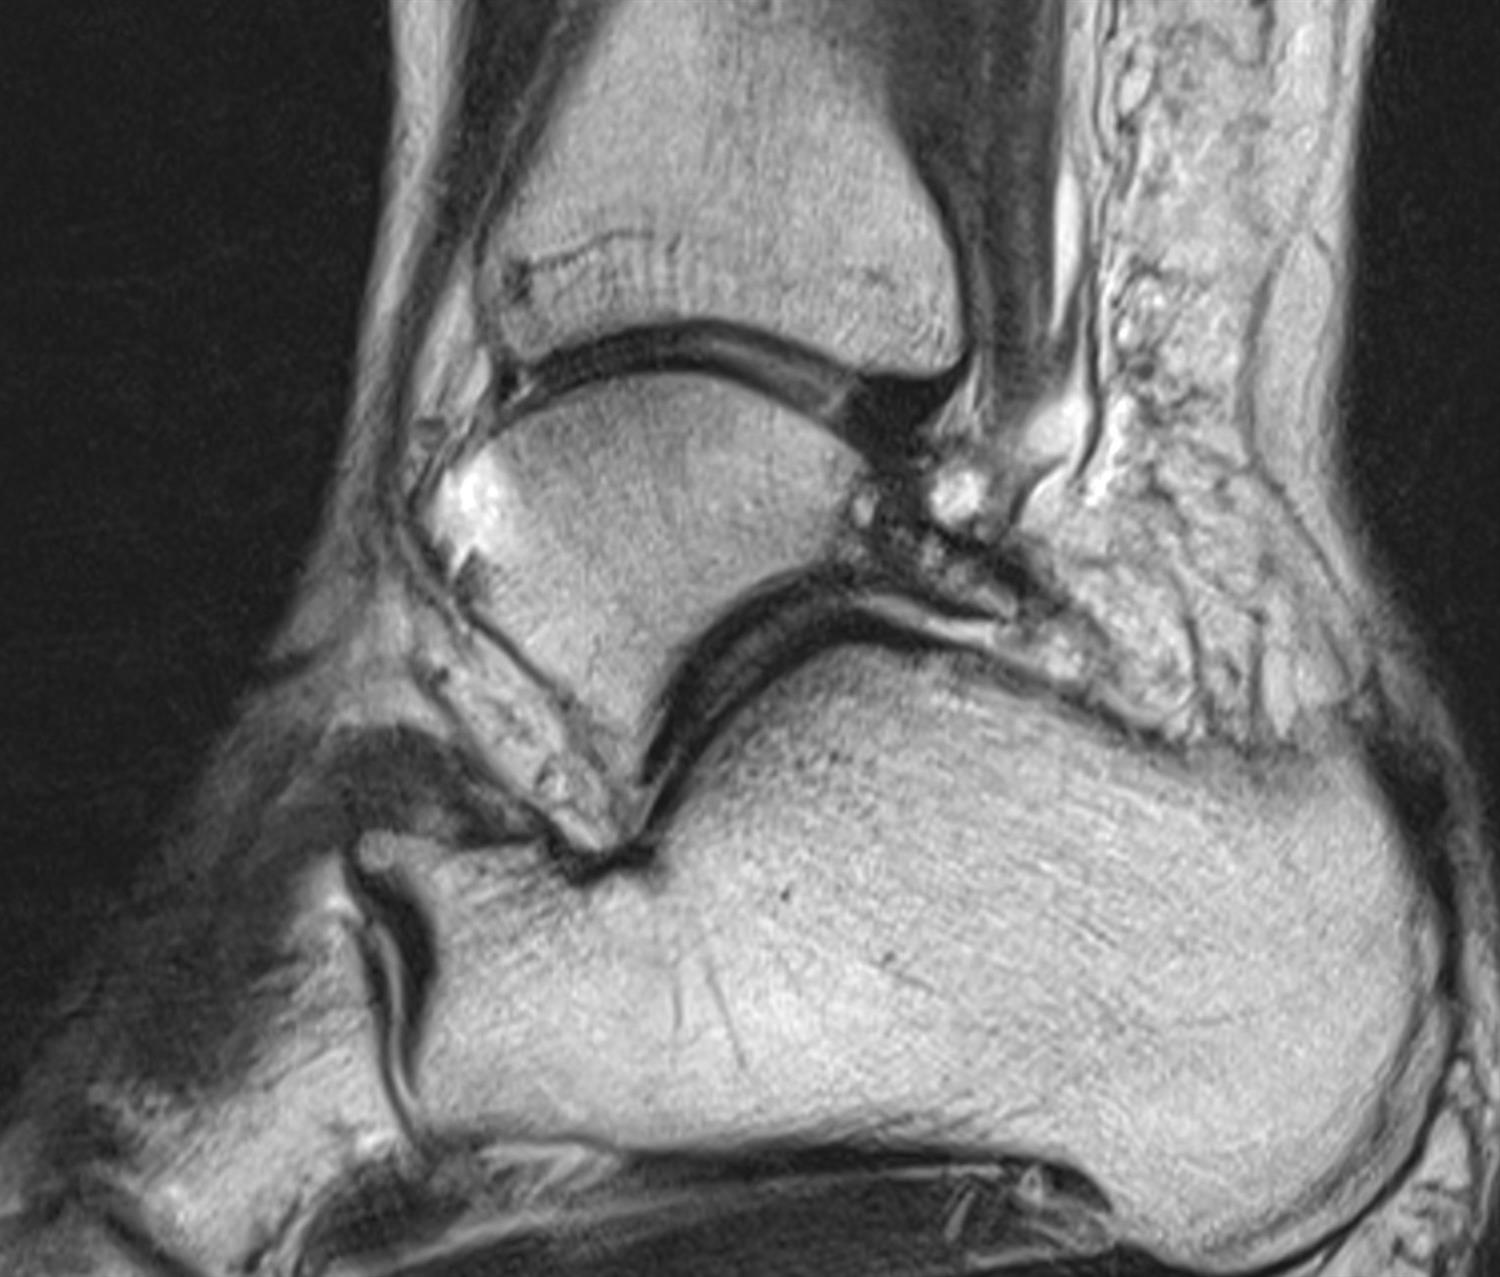

• MRI

• findings

• shows os trigonum and associated inflammation and edema in FHL tendon